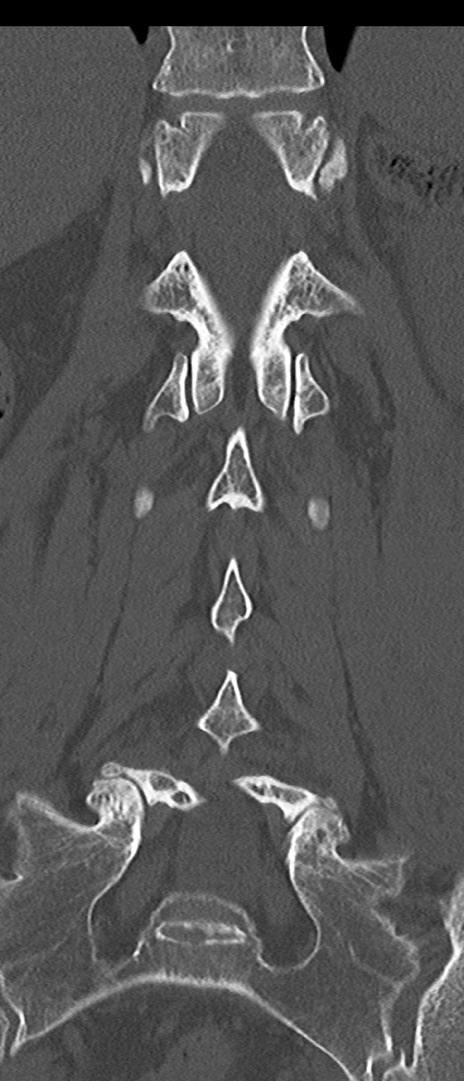

腰椎CT

矢状断像